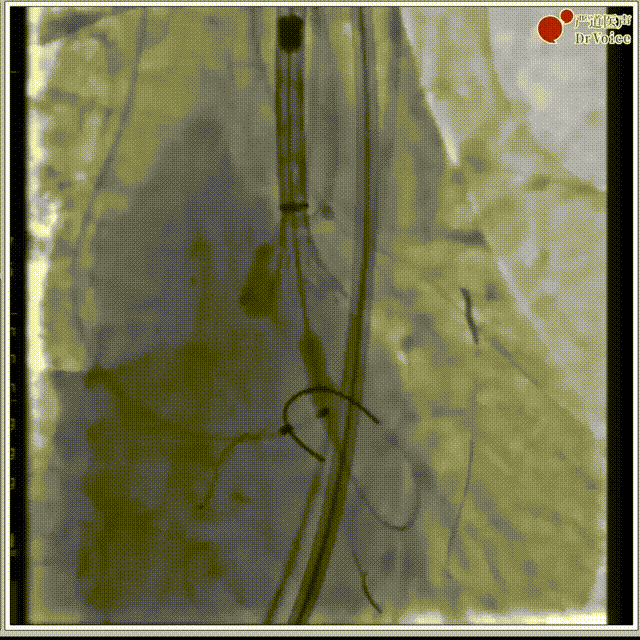

2. 冠脉保护,左冠预埋支架。

冠脉保护后造影

4. 植入23mm Evolut PRO瓣膜,过弓及瓣膜定位。

过弓,植入瓣膜

主动脉根部造影